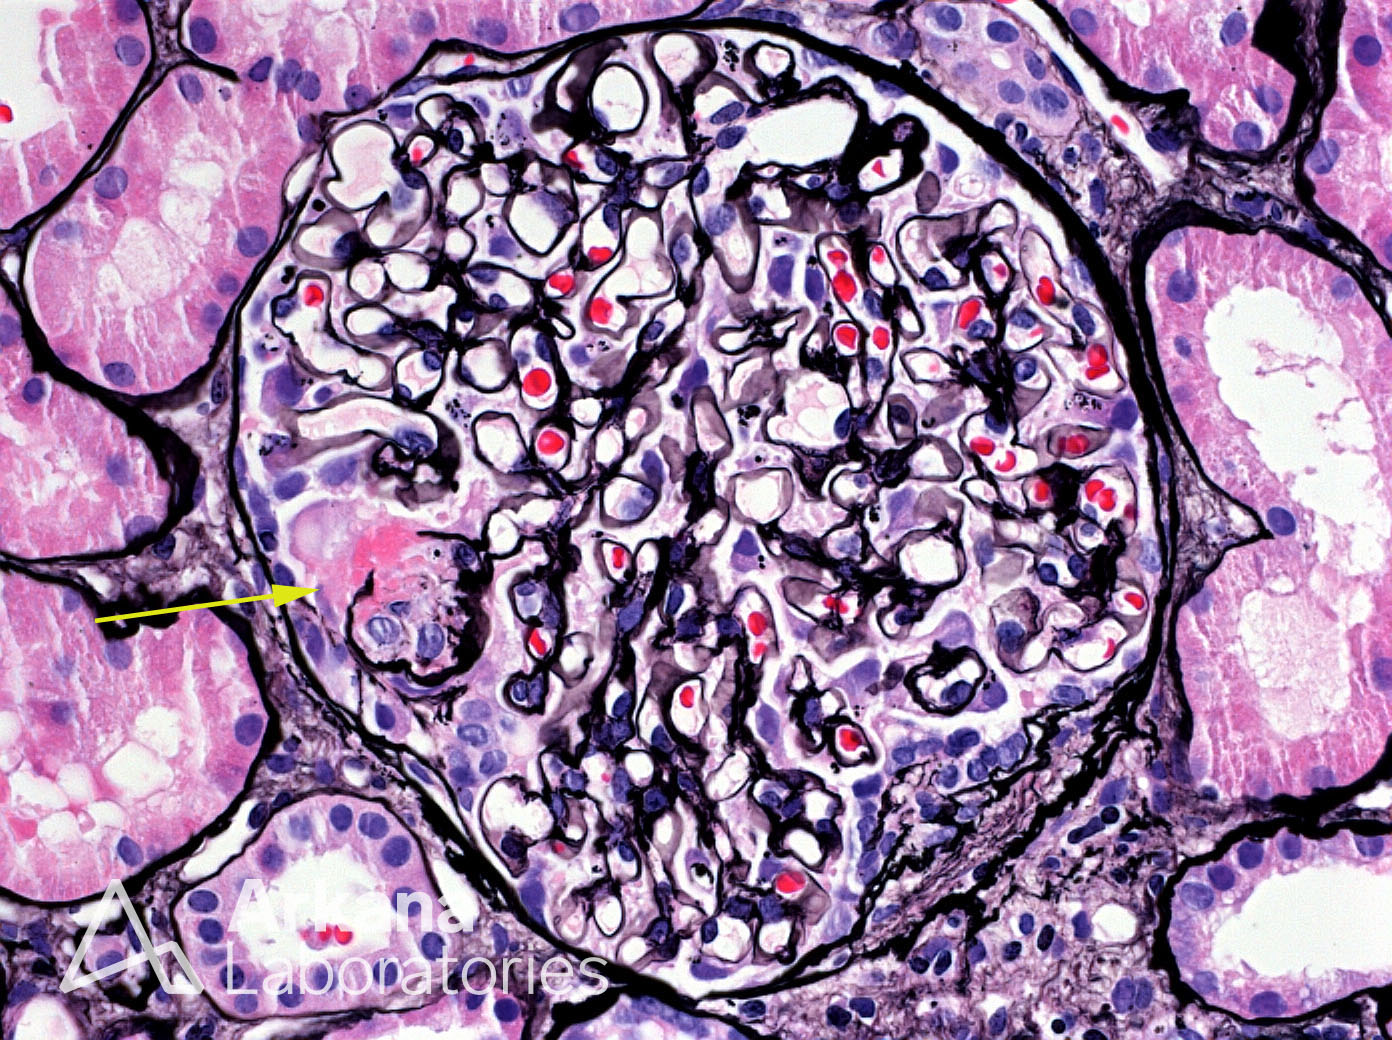

Glomerulus with Segmental Necrotizing Lesion